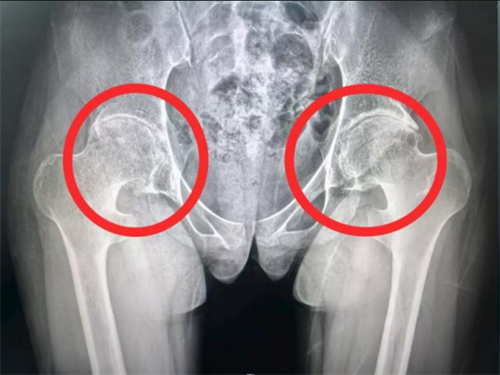

X片显示双侧髋关节间隙严重狭窄、软骨溶解,髋关节屈曲挛缩畸形

运动医学科团队接过了这个沉重的接力棒。在她14岁那年,运动医学科李良军主任考虑患者年龄太小,不适合进行关节置换,尝试为小雨进行了一次髋关节镜微创手术,进行了髋关节清理、髋关节撞击成形、滑膜活检术,虽然症状短期内有所缓解,但因为股骨头和髋臼软骨大部分已经溶解,一年后髋关节疼痛很快复发。今年6月份小雨再次就医时,李良军主任带领的医学团队经过多番讨论,考虑到小雨目前双侧髋关节处于屈曲挛缩畸形,双侧髋关节的软骨已经溶解,关节间隙明显狭窄,要想让她恢复正常行走,只有进行人工髋关节置换才是唯一的选择。